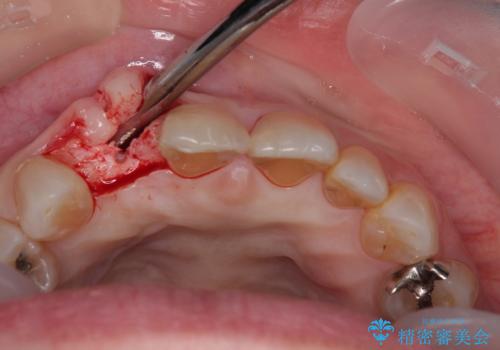

- 前歯のインプラント治療を検討して様々医院を探していたところ、1回の手術で治療ができるとのことで来院された患者様です。

長期間の治療と外科処置の回数が多くなることを懸念して、なかなかインプラント治療に乗り出せなかったそうですが、1DAYインプラントというものがあることを知り、当院にいらっしゃいました。

仮歯を事前に用意し、インプラント埋入時に即日で仮歯を装着する、即時荷重インプラントの計画で治療を進めて行くこととしました。